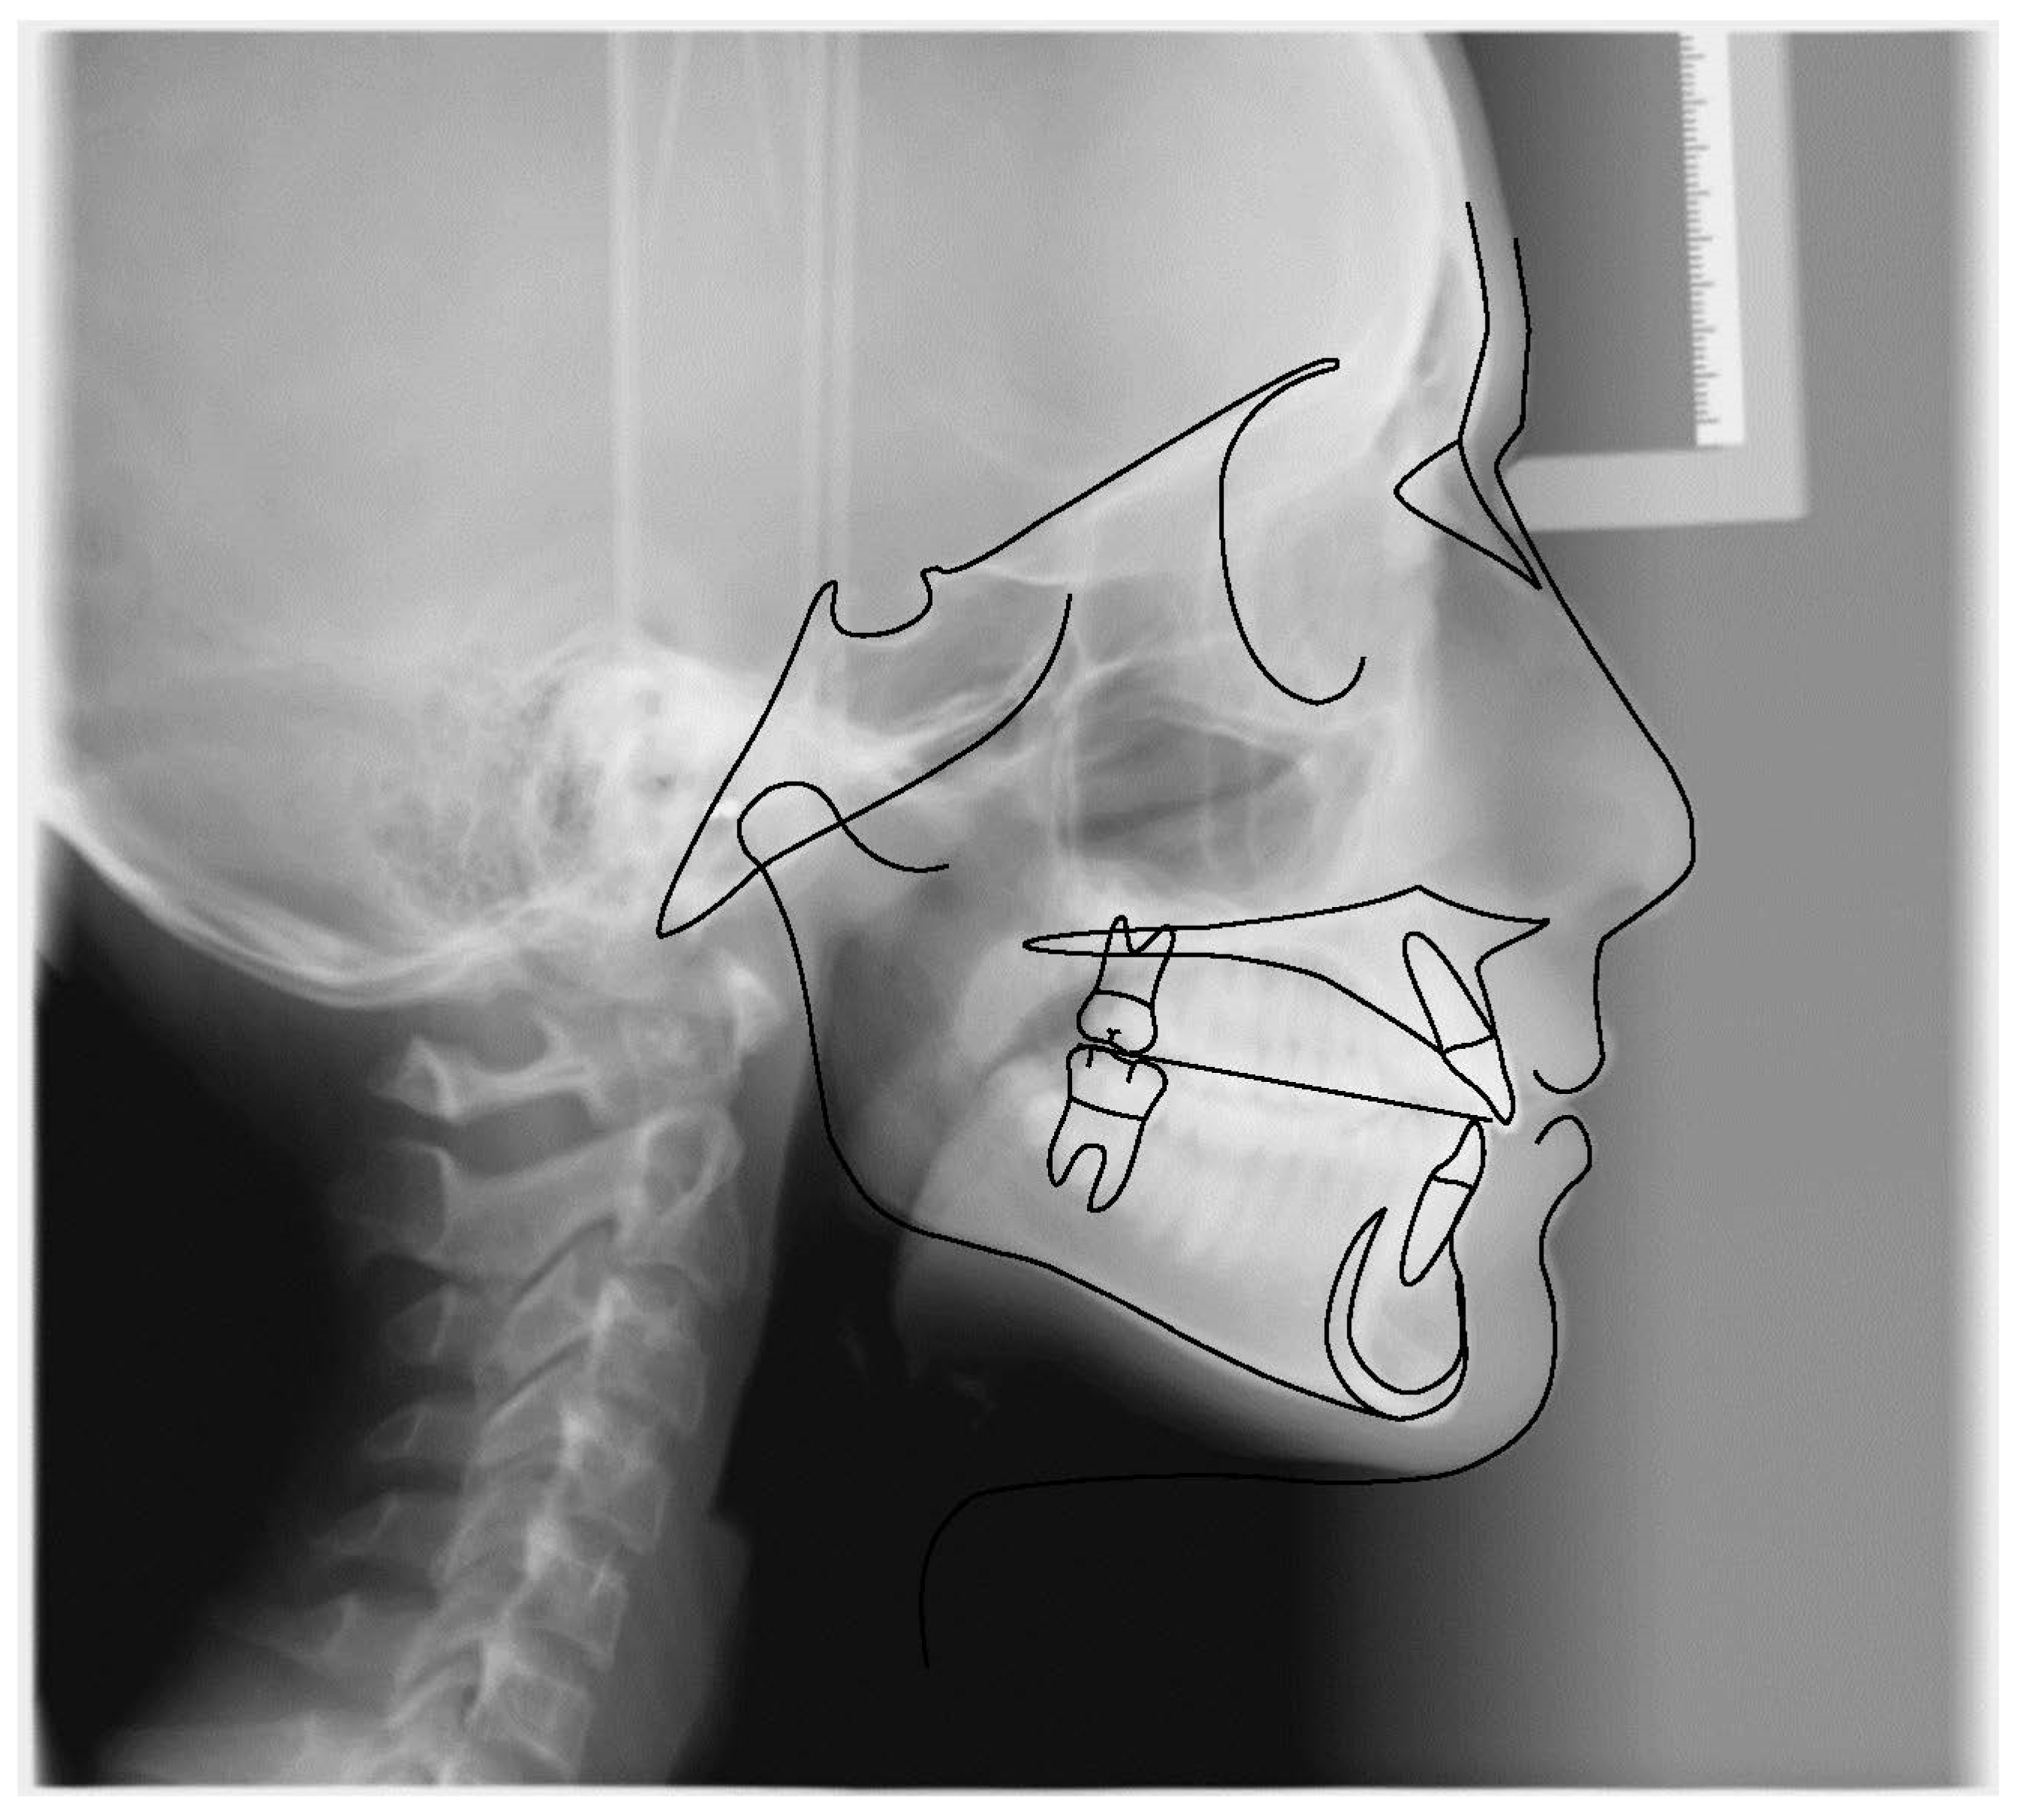

3.1. Clinical Case #1

3.2. Clinical Case #2

3.3. Clinical Case #3

3.4. Clinical Case #4